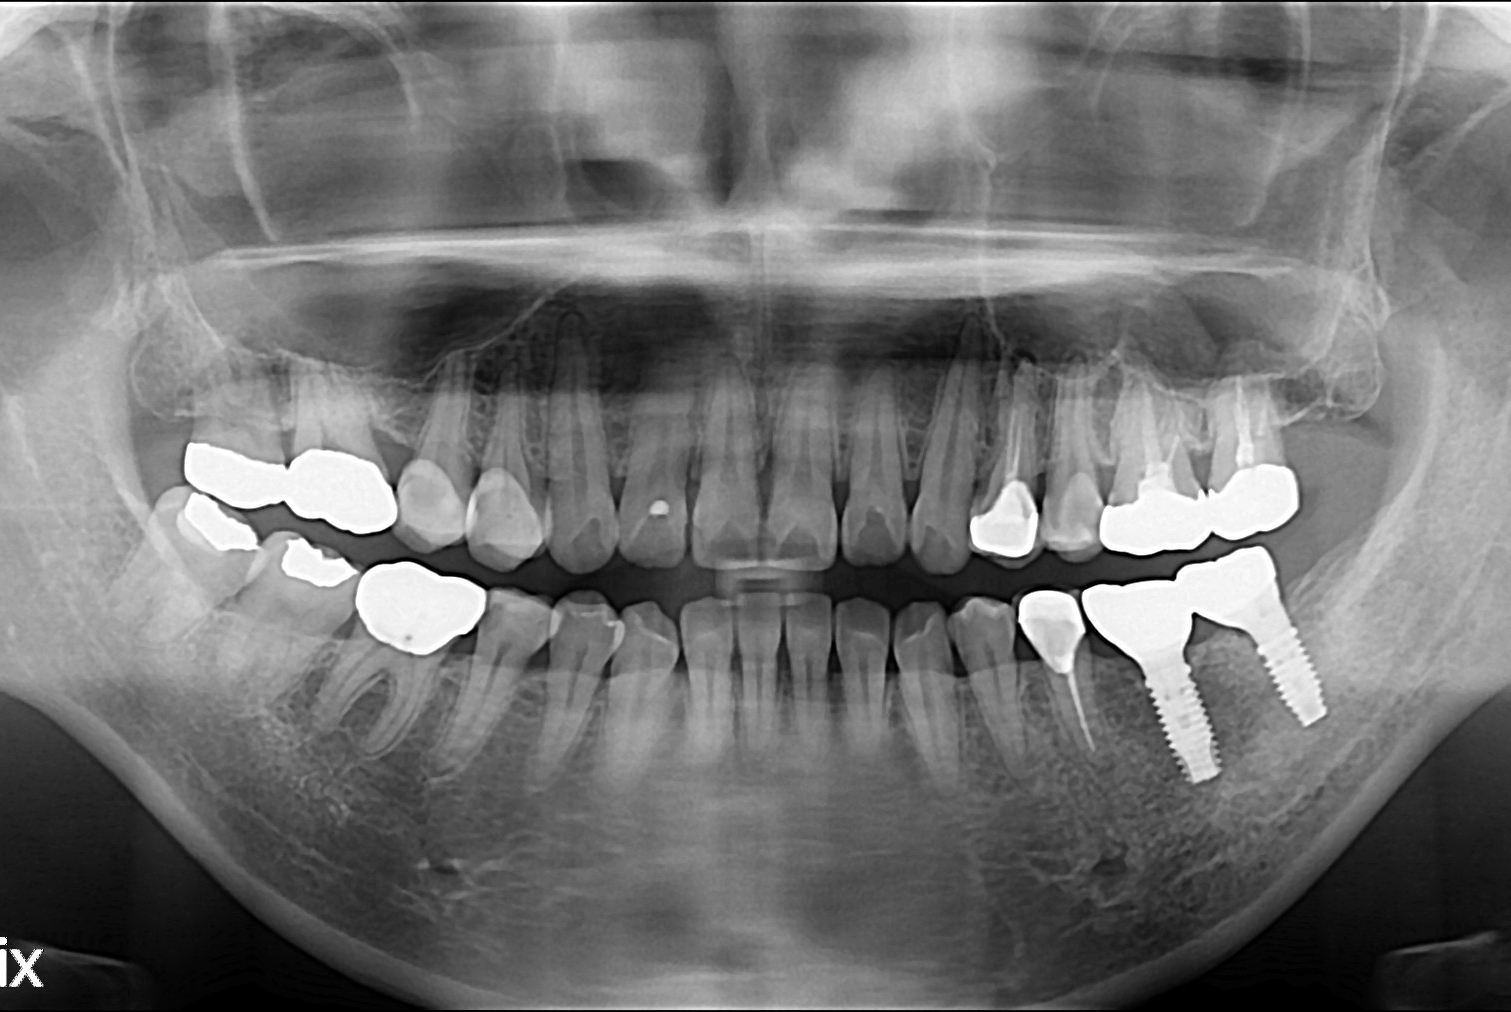

치료전 : 2017-01-21

정은이 후.jpg

치료후 : 2017-02-18

세종치과는 많은 환자와 다양한 케이스를 바탕으로 항상 편안한 임플란트 수술을 제공하고자 노력하고,

오래동안 튼튼히 쓸 수 있는 임플란트 수술을 가장 큰 목표로 삼고 있습니다